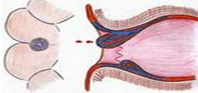

痔瘡有(yǒu)什(shén)麽症狀?不(bù)治療會(huì)有(yǒu)什₩φ✔₽(shén)麽危害?